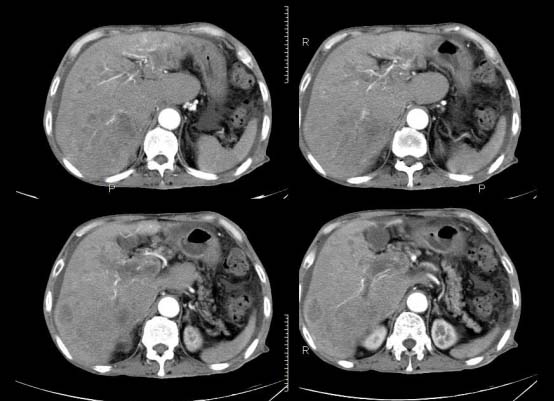

以下是引用杀毒软件在2010-3-30 18:11:00的发言:[br]考虑---hcc侵犯侵犯周围组织〔胰腺、胆管、肠系膜上动静脉〕伴门脉、下腔静脉癌栓形成、动-静脉瘘、肝门、腹腔动脉周围淋巴结转移可能性大、腹水。

以下是引用pujunzhi在2010-3-31 8:45:00的发言:[br]支持 肝癌并多发肝内转移,胰头、肝门、腹腔动脉周围淋巴结转移,下腔静脉癌栓形成,肝硬化、腹水。

以下是引用jsgdoctor在2010-3-30 20:42:00的发言:[br]考虑---hcc侵犯侵犯周围组织〔胰腺、胆管、肠系膜上动静脉〕伴门脉、下腔静脉癌栓形成、动-静脉瘘、肝门、腹腔动脉周围淋巴结转移可能性大、腹水。